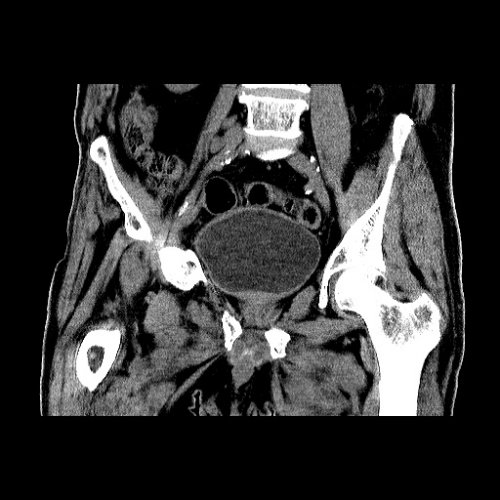

CT Angiogram for evaluation of severe hematochezia

From emcrit.org

CT Angiogram for evaluation of severe hematochezia Medical Test Cta It can be used to determine. a computed tomography (ct) angiogram is a test to view your blood vessels and tissues. a computerized tomography (ct) coronary angiogram is an imaging test that looks at the arteries that supply blood. computed tomography angiography (cta) uses an injection of contrast material into your blood vessels and ct scanning to. Medical Test Cta.

From www.researchgate.net

Computed tomography with angiography (CTA) scan of the abdomen and Medical Test Cta It can be used to determine. a computerized tomography (ct) coronary angiogram is an imaging test that looks at the arteries that supply blood. During the test, your provider injects a dye that highlights your blood. a computed tomography (ct) angiogram is a test to view your blood vessels and tissues. computed tomography angiography (cta) uses an. Medical Test Cta.